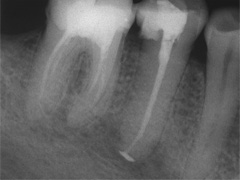

Aufbissempfindlichkeit an 33 veranlasste uns erstmalig in dieser Kieferregion zu röntgen. Mit grossen Augen sahen wir dann an, was uns auch ansah. Einen Knochendefekt dieser Grössenordnung mit seiner schaurigen Aura sieht man zum Glück nicht jeden Tag. Doch, obgleich das Alien dereinst Zahn 34 entsprang, war eine Behandlung nur am Zahn davor durchsetzbar. Dessen Wurzelfüllung erfolgte regulär nach 14 Tagen, neue Terminangebote aber wurden, weil angeblich nicht mehr nötig, verschmäht.

Keine 8 Wochen gingen noch in's Land, bis das mit Macht geschah, was lange schon erwartet war. Das Arbeitsprogramm bestand aus Eröffnung von Zahn 34 und einer Schwellung inkl. Drainage, am nächsten Tag dann noch Aufbereitung des Kanals mit Einlage. 2 Wochen später dann die Füllung plus einem als Resektion deklarierten Auslöffeln des Granu­lationsgewebes durch eine Mini-Öffnung, zu deren Verschluss eine Naht genügte.

3 Aufnahmen sind von 2001, die vierte vom Nov. 2006